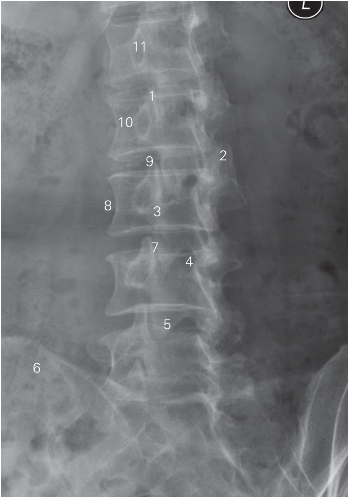

图6-4 腰椎正位DR平片

1 第1腰椎椎体 1st lumbar vertebral body

2 棘突 spinous process 3 横突 transverse process

4 L3/4椎间隙 L3/4 lumber intervertebrale space

5 髂骨 ilium 6 骶骨 sacrum

7 骶髂关节 sacroiliac joint 8 骶骨翼 sacral wing

9 上关节突 superior articular process

10 下关节突 inferior articular process 11 椎弓根 vertebral pedicle

12 关节突关节 zygapophyseal joint